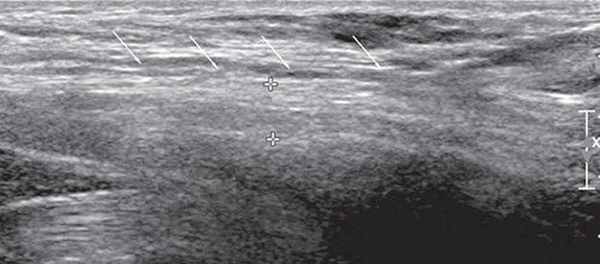

УЗИ бедренного нерва проводили в положении пациента лежа на спине. Бедренный нерв визуализировали в паховой области латеральнее сосудистого пучка от уровня паховой связки до верхней трети бедра (рис. 2, 3). Исследование проводили в поперечной и продольной плоскостях сканирования (рис. 2, 4).

Рис. 4. В-режим. Исследование правого бедренного нерва в продольной плоскости сканирования на уровне паховой области и верхней трети бедра: стрелки - бедренный нерв.